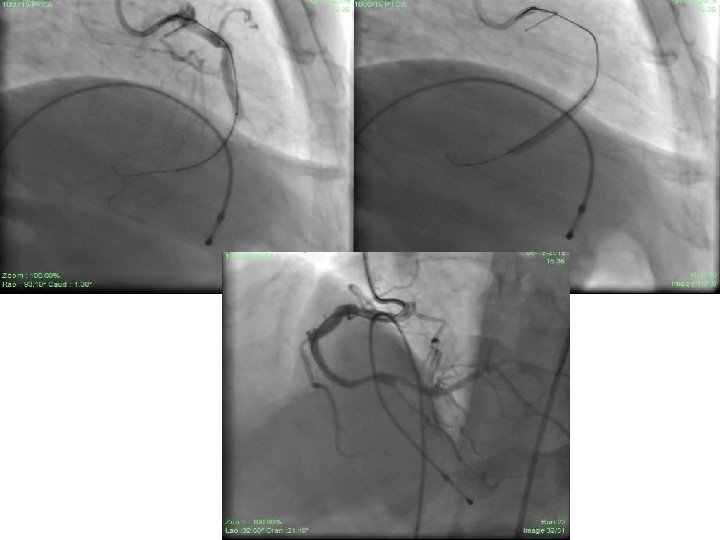

• Patient was taken up for PCI to RCA and LAD through RFA access under TPI. • RCA hooked initially with JR 3. 5/6 F guiding catheter then AL 1/6 F guiding catheter. • Lesion finally crossed with Miracle-3 wire using balloon support. • Lesion dilated with 1. 25 X 8 mm CTO balloon and 2. 0 X 15 mm Sprinter Legend balloon. • Xience-V 2. 75 X 28 mm stent deployed successfully in distal RCA with normal flow through and beyond stent. • TIMI – III flow achieved. • 50% residual stenosis remained distal to stent at crux and PLV.

• In the same sitting, bifurcation lesion in LAD was tackled. • Using JL 3. 5/6 F guiding catheter, lesion crossed with BMW guide wire in LAD (D 1 could not be entered in spite of repeated attempts). • Angioplasty to LAD done with 2. 0 X 15 mm S. L. balloon. • Xience-V, 2. 75 X 23 mm was deployed in LAD. • D 1 was pinched with TIMI – I flow though there was normal flow through and beyond stent in LAD with TIMI –III flow. • Intra- coronary bolus and i. v. infusion of Tirofiban was used. • Patient was pain free and no ECG changes were seen. • Discharged on day 3 from hospital and continued on conventional anti anginal therapy.